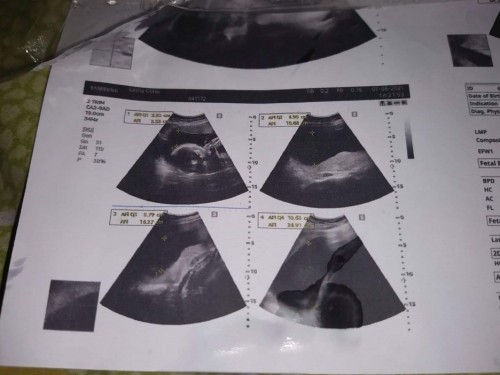

#ขอคำแนะนำหน่อยค่ะ ตอนนี้ตั้งครรภ์ ได้ 25 สัปดาห์ แล้ววันนี้ไปซาวด์ 4 มิติมา พบว่าน้องมีปัญหาเรื่องปอด หมอบอกว่า มีก้อนเบียดหัวใจน้องไปอีกฝั่งนึง แบบนี้หมอจะสั่งยุติการตั้งครรภ์ไหมคะ แล้วพอจะมีทางรักษาให้น้องเป็นปกติได้ไหม #ขอบคุณล่วงหน้านะคะ